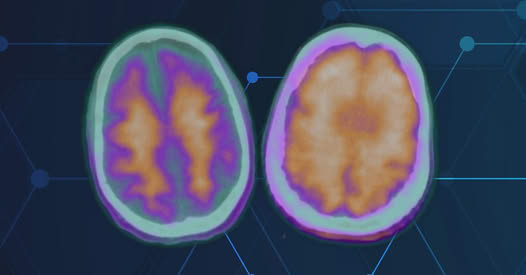

“They find the amyloid in the brain, and they attach to it,” Schulz explained. “That turns on the white blood cells, which then literally eat the amyloid plaques. By a year and a half (of treatment), most people don’t have any amyloid present on their amyloid PET scan.”

It’s not a cure but it helps reduce mental decline. In some cases, patients show cognitive improvement.